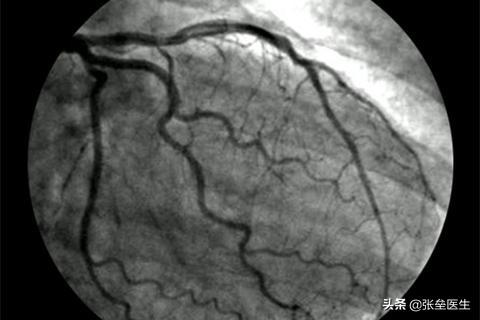

⑤导管及心血管造影检查:用于其它诊断手段难以确诊的心脏疾病。目前冠状动脉造影是诊断冠状动脉粥样硬化性心脏病的“金标准”,可以明确冠状动脉有没有狭窄、狭窄的部位、程度、范围,并为治疗方法提供依据,同时可以进行左心室造影,对心功能进行评估。